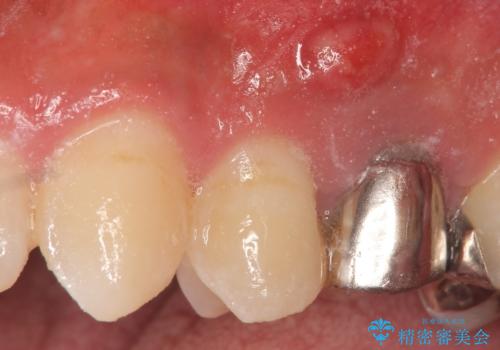

- 歯茎にできものが出来てなかなか治らないので診て欲しいといらっしゃった方の症例です。

診査の結果、左上4番目の歯の神経が死んでおり、根尖に膿が溜まっていることが原因とわかりました。

そのため左上4番目の歯は根管治療を行い、歯茎の膿の出口の消失を確認後、オールセラミッククラウンによる補綴を行いました。